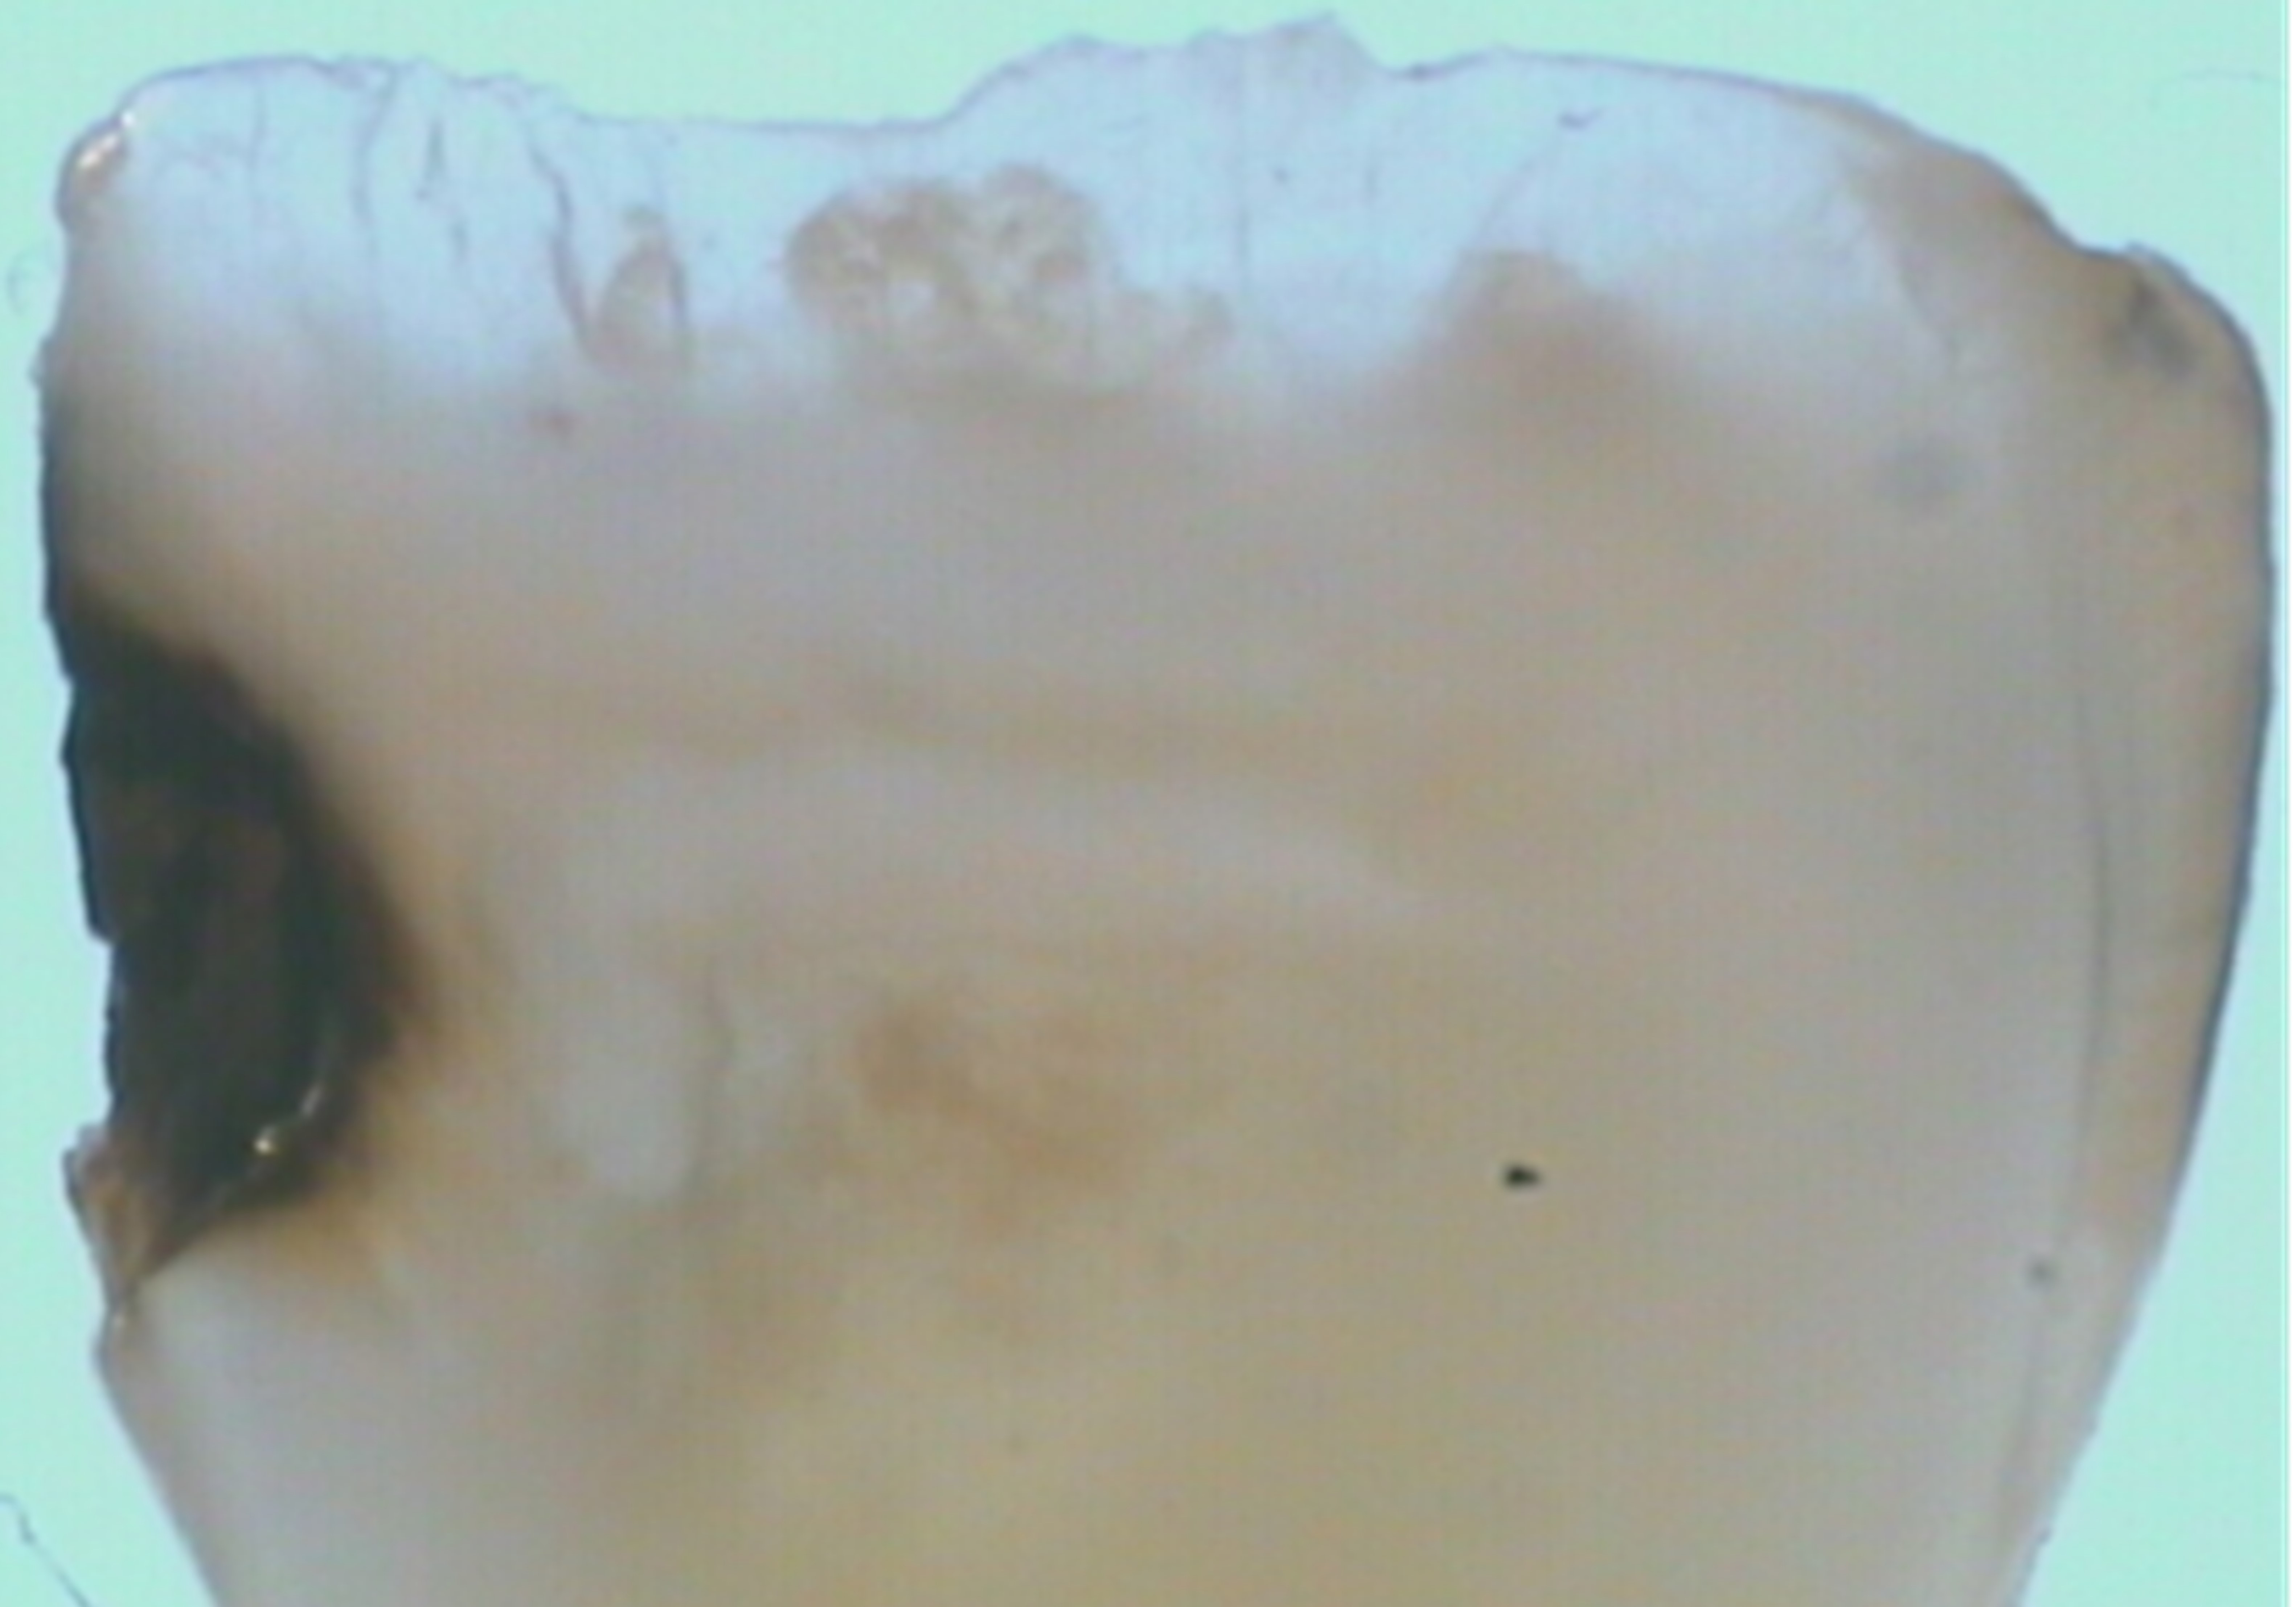

There are several advantages of using SDF in dental treatment. First, it showed an antimicrobial activity against mono-species, dual-species, and multi-species cariogenic biofilm.14-16 Silver ions are bactericidal metal cations that inhibit biofilm formation.17 Studies have indicated that silver interacts with sulfhydryl groups of proteins and DNA, thus altering hydrogen bonding and inhibiting respiratory processes, DNA unwinding, cell-wall synthesis, and cell division.18 At the macro level, these interactions affect bacterial killing and inhibit biofilm formation.17 Second, fluoride promotes caries lesion remineralization. Fluoride has been indicated to react with hydroxyapatite and generate calcium fluoride, which is a reservoir of fluoride, and facilitate further remineralization.19 An ex vivo study reported surface microhardness of the surface layer of the arrested caries after SDF applications was comparable with the unaffected sound dentin20 (Figure 1 and Figure 2). This is consistent with another study, in which a high remineralized zone was observed on the surface of arrested caries from exfoliated teeth with SDF treatment21 (Figure 3 and Figure 4). Third, its application procedures are simple and do not require injection or drilling, and the treatment does not involve expensive support infrastructure equipment such as piped water and electricity. The simplicity of the treatment is conducive to treating caries in apprehensive young children who may have intense dental fear, uncooperative patients with special needs, or elderly patients who have difficulty adapting to traditional dental care. It also allows trained workers to deliver the treatment to people who live in the area but who may not be able to easily access dental service.22 Patient compliance and satisfaction is often good when the patient is provided a clear explanation of the treatment outcome.23,24 Finally, the cost of SDF treatment is low and should be affordable in most communities.

Fig 2. Ground section of a primary incisor with arrested caries lesion after SDF treatment: microhardness of dentin (in median Knoop hardness number) in soft and SDF-arrested caries according to the distance from the lesion surface. (image from Chu and Lo, 2008, ref 20 [reprinted with approval])

Figure 2